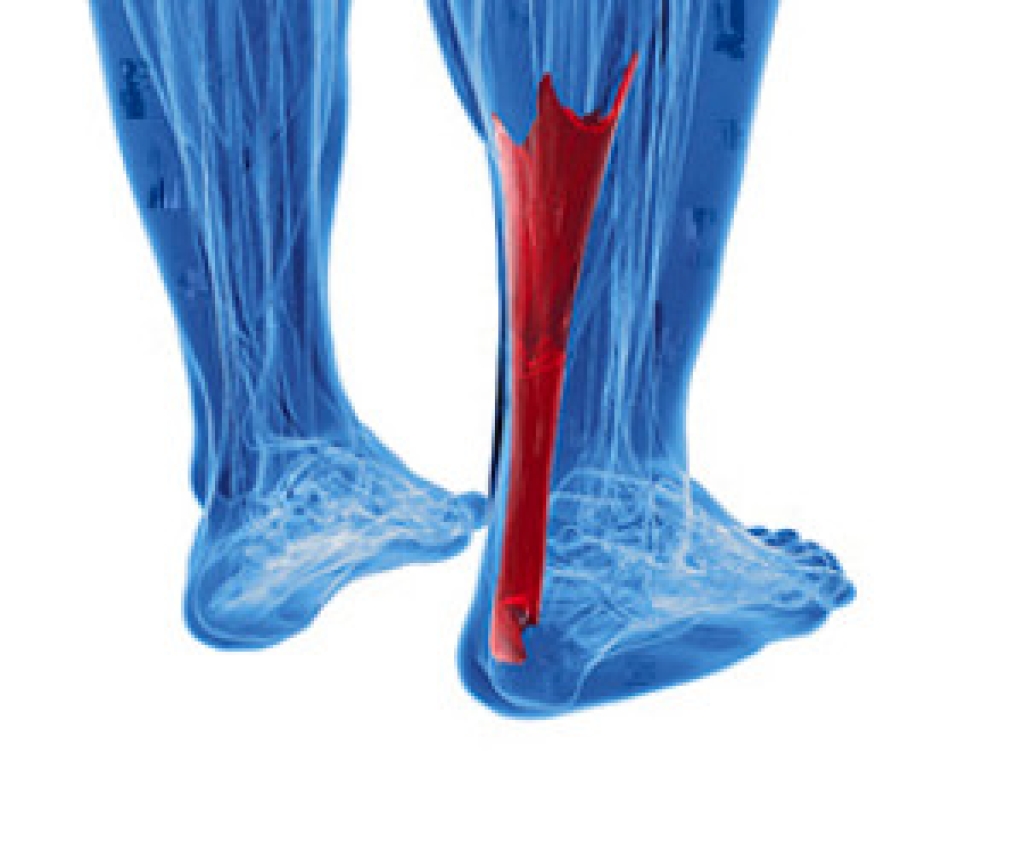

How to Deal With Achilles Heel Pain

When your Achilles tendon, which connects the calf muscles to the heel bone, is overused, the area may become inflamed. This is a condition known as insertional Achilles tendonitis. In active adults, it is often caused by repetitive use through running or jumping. Symptoms include a sharp pain in the back of the heel, or in some cases, a dull ache. The area will be tender to the touch, and redness and swelling often develops. The first thing you can do is to rest the foot and apply ice to reduce pain and swelling. Try not to rub or poke the area. Non-steroidal anti-inflammatory medication, which can be prescribed by a podiatrist, may help to reduce the inflammation. Once inflammation in the area has diminished there are a number of exercises you can do to strengthen the calf muscles. This will be key to keep from developing chronic tendonitis of the tendon. It is a good idea to visit a podiatrist for a full diagnosis, treatment options, and a list of exercises you can do.

Achilles tendon injuries need immediate attention to avoid future complications. If you have any concerns, contact one of our podiatrists of Pennsylvania Foot & Ankle. Our doctors can provide the care you need to keep you pain-free and on your feet.

What Is the Achilles Tendon?

The Achilles tendon is a tendon that connects the lower leg muscles and calf to the heel of the foot. It is the strongest tendon in the human body and is essential for making movement possible. Because this tendon is such an integral part of the body, any injuries to it can create immense difficulties and should immediately be presented to a doctor.

What Are the Symptoms of an Achilles Tendon Injury?

There are various types of injuries that can affect the Achilles tendon. The two most common injuries are Achilles tendinitis and ruptures of the tendon.

Achilles Tendinitis Symptoms

• Inflammation

• Dull to severe pain

• Increased blood flow to the tendon

• Thickening of the tendon

Rupture Symptoms

• Extreme pain and swelling in the foot

• Total immobility

Treatment and Prevention

Achilles tendon injuries are diagnosed by a thorough physical evaluation, which can include an MRI. Treatment involves rest, physical therapy, and in some cases, surgery. However, various preventative measures can be taken to avoid these injuries, such as:

• Thorough stretching of the tendon before and after exercise

• Strengthening exercises like calf raises, squats, leg curls, leg extensions, leg raises, lunges, and leg presses

If you have any questions please feel free to contact one of our offices located in Bensalem, Philadelphia, Northeast Philadelphia, Yardley, PA, and Hamilton, NJ . We offer the newest diagnostic tools and technology to treat your foot and ankle needs.

Read more about Achilles Tendon Injuries